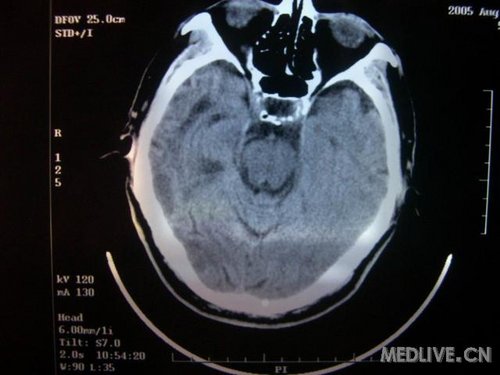

病人男性 73岁 市民 以“幻听、幻视两天,言语含糊、精神错乱一天”入院。

两天前无诱因出现幻听、幻视,描素眼前有彩色的圆圈,听见有人说话(但说什么不详),一天前出现胡言乱语,言语含糊,精神错乱,问话不答,行走略有不稳,来我院就诊,门诊头CT检查:(下面有片)入院后查体不合作,表情淡漠,问话不答,大致检查了一下,颅神经未见明显异常,颈软,右手活动似忽略差。其他检查不配合。脑电图:广泛轻-中度异常。

既往史:半年前曾患“右侧脑梗塞”但无明显后遗症,生活能自理,无高血压、糖尿病、心脏病史。

先传半年前的片子:

此次入院时的片子: